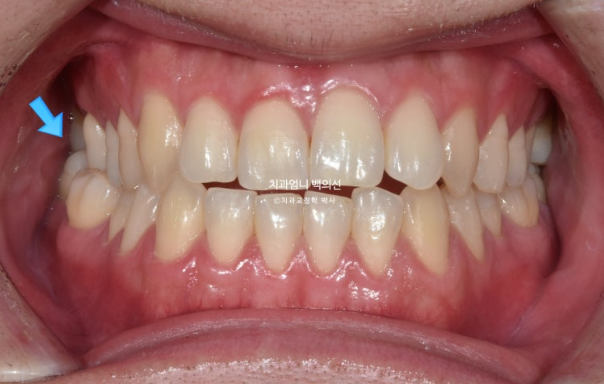

This is what it looked like in January 2023, one month after the initial visit, with the expansion device in place.

The palatal expansion device installed in the palate is not visible from the front.

Expansion began in January 2023, and in February, although the suture had not yet opened, the expansion device could no longer turn. A minor procedure called corticopuncture was performed to actively promote separation of the palatal suture.

After that, expansion was successful in March, creating a large space between the front teeth.